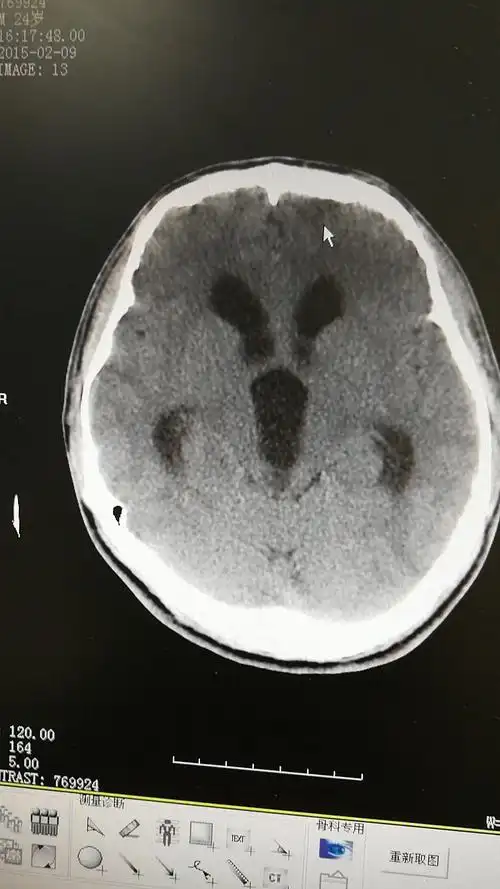

脑积水的症状,诊断及治疗 - 好大夫在线